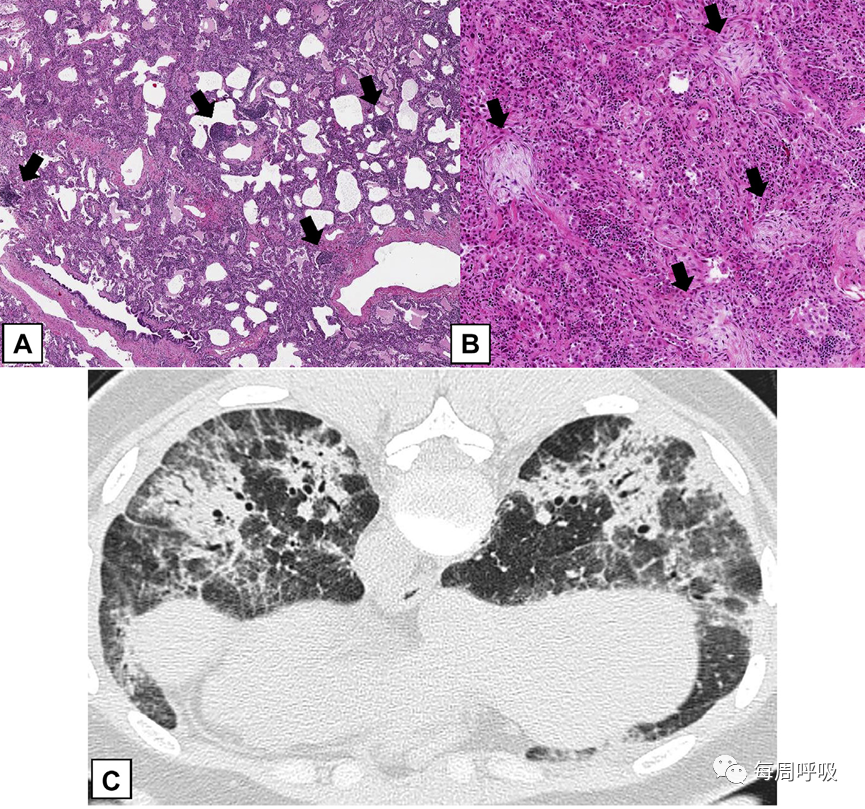

OPP的组织学特征可以在各种情况下遇到。尽管潜在疾病有时在活检标本上表现出提示性特征,但仅通过组织学检查可能无法将COP与SOP区分开来。在某些情况下,肺组织的组织学活检,即使是大量的外科肺活检标本,也会产生误导。标本可能只显示极少量的OPP和大多数其他发现,如NSIP(图22)。在这些病例中,除非CT扫描进行影像学-病理相关性检查,否则可能忽略主要的肺实变累及,提示OPP的初步诊断。

图22继发性机化性肺炎(OP):影像学-病理相关性。A,外科肺活检标本上,这个病人患有干燥综合征,以非特异性间质性肺炎(NSIP)为主要病变类型。淋巴细胞和浆细胞弥漫性间质浸润,导致肺泡壁轻度增厚。有许多淋巴聚集(箭头)。B,局灶性OP表现为远端气腔内疏松结缔组织的息肉样栓子(箭头)。C,患者俯卧位的轴位CT扫描显示支气管周围的实变区域,并伴有OP特有的支气管充气征。还注意到双侧磨玻璃影和网状影,提示NSIP。外科活检结果显示以NSIP为主,轻度局灶性OP。活检标本的OP程度被低估,可能是因为它位于支气管周围且远离胸膜,而NSIP模式主要累及胸膜下区域。该病例的影像学和病理相关性表明,CT扫描结果优于外科肺活检结果,在这种临床情况下,诊断为干燥综合征相关的继发性OP。

临床OP (COP或SOP)必须通过多学科方法与活检标本中观察到的组织学或影像学OPP进行鉴别,或通过CT扫描作为其他ILDs的组成部分或作为非特异性反应性病变进行鉴别(表4)。在ILDs中,OPP可被视为:(1)在ILDs(如UIP、NSIP或HP)中出现的轻微病变;(2)作为组织型急性肺损伤的组成部分,如DAD;(3)作为UIP或特发性肺纤维化或各种其他ILDs(包括NSIP或HP)急性加重的表现,在活检标本和/或CT扫描中也存在这些慢性ILDs的基础疾病;(4)肺损伤的混合模式,特别是NSIP合并OP或嗜酸粒细胞性肺炎合并OP。通过CT扫描和/或活检很难区分OPP和嗜酸性粒细胞肺炎,特别是如果患者在活检前接受了糖皮质激素,导致组织中嗜酸性粒细胞数量显著减少。

在病变主要是OPP的病例中,应评估活检标本是否有提示SOP潜在病因的特征,如显著的慢性间质性炎症(药物毒性、胶原血管疾病[图22])或放射性肺炎。最后,OPP必须与其他ILD相区别,尤其是DAD的机化期,该期表现为明显的腔内出芽纤维化,与OPP相似。DAD与OPP的区别在于肺受累呈弥漫性而非斑片状(图25A、25B),常伴有反应性细胞异型性(图25B)、机化性纤维化导致间质增厚(图25A、25B)、透明膜(图25A)和/或急性炎症和出血灶。与DAD患者不同,COP患者通常可游走,胸部影像学显示如上所述的斑片状结节性浸润(图26)。

NSIP与COP相关的OPP相比表现出更明显的慢性间质炎症。OP病灶常出现在NSIP中,但它们是局灶性的,而不是主要的组织学表现。鉴于CT扫描结果可能提示COP或SOP等其他诊断,因此活检标本显示NSIP模式时,影像学与病理学的相关性很重要(图22)。换句话说,CT扫描结果可以更准确地反映主要病变(OP或NSIP)是什么,即使在活检标本中,包括外科肺活检标本可能不能准确地反映主要病变类型。